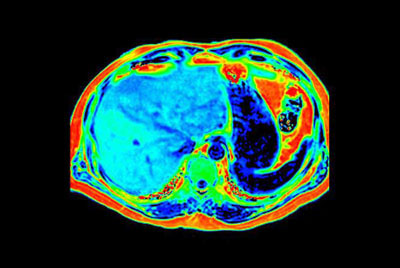

SmartSpeed Liver

Liver quantification

Fatty liver with MR Elastography